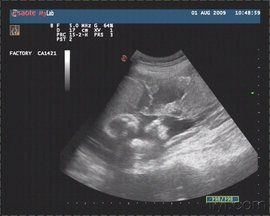

胎盤血池(也稱胎盤靜脈池)在胎盤絨毛中心部分無絨毛處,胎盤實質中的較大的近圓形暗區,可見細密光點從側壁流入暗區內,若範圍大,將影響絨毛血流的交換。

胎盤血竇,也稱為胎盤靜脈池(血池),指在胎盤絨毛中心部分無絨毛處,胎盤實質中的較大的近圓形暗區,可見細密光點從側壁流入暗區內。